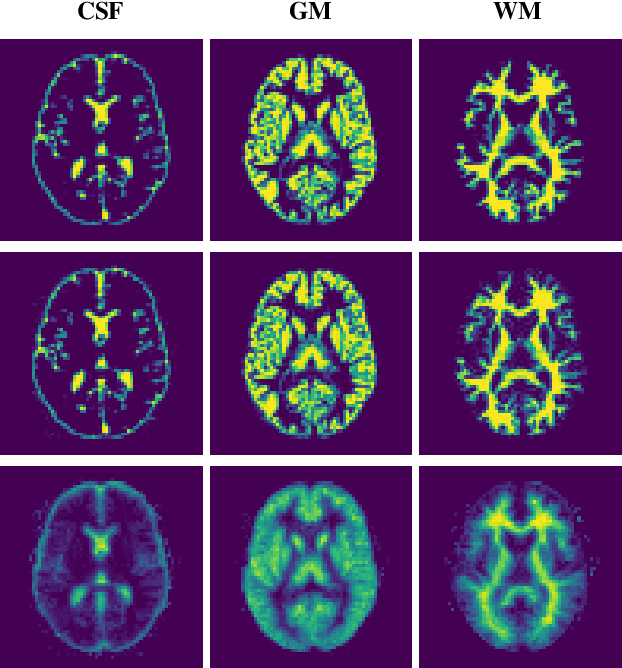

Abstract:Reconstructing digital brain phantoms in the form of multi-channeled brain tissue probability maps for individual subjects is essential for capturing brain anatomical variability, understanding neurological diseases, as well as for testing image processing methods. We demonstrate the first framework that optimizes brain tissue probability maps (Gray Matter - GM, White Matter - WM, and Cerebrospinal fluid - CSF) with the help of a Physics-based differentiable MRI simulator that models the magnetization signal at each voxel in the image. Given an observed $T_1$/$T_2$-weighted MRI scan, the corresponding clinical MRI sequence, and the MRI differentiable simulator, we optimize the simulator's input probability maps by back-propagating the L2 loss between the simulator's output and the $T_1$/$T_2$-weighted scan. This approach has the significant advantage of not relying on any training data, and instead uses the strong inductive bias of the MRI simulator. We tested the model on 20 scans from the BrainWeb database and demonstrate a highly accurate reconstruction of GM, WM, and CSF.